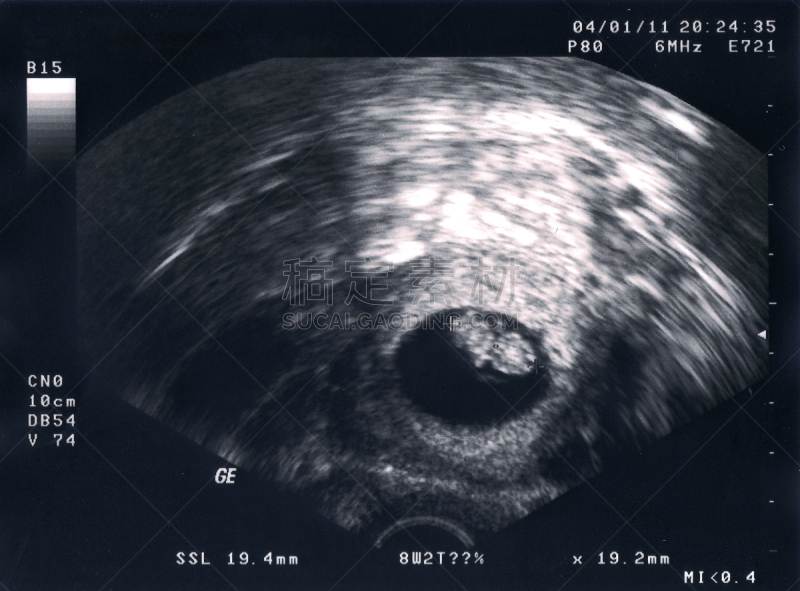

一个孩子在超声波机上详情

孕妇和超声波扫描详情

孕妇胎儿超声检查。详情